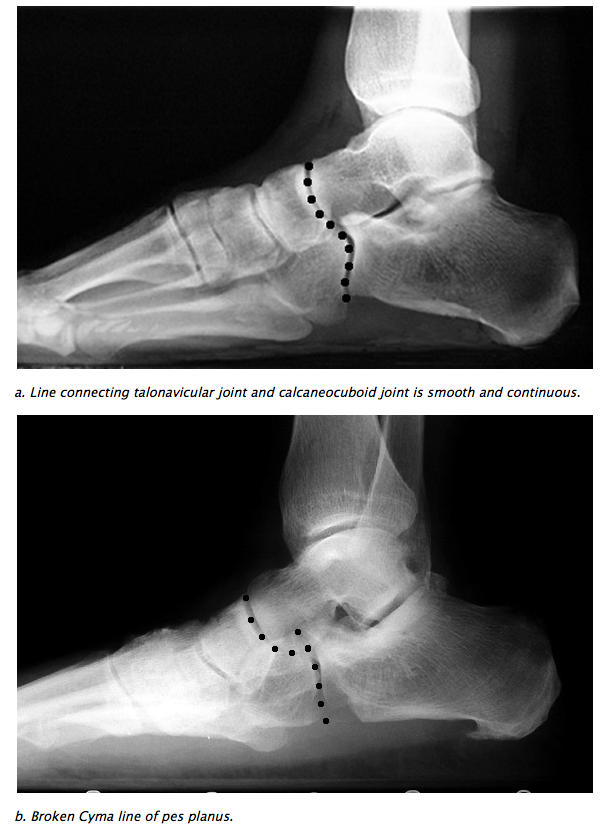

• AP & Lateral: CYMA line